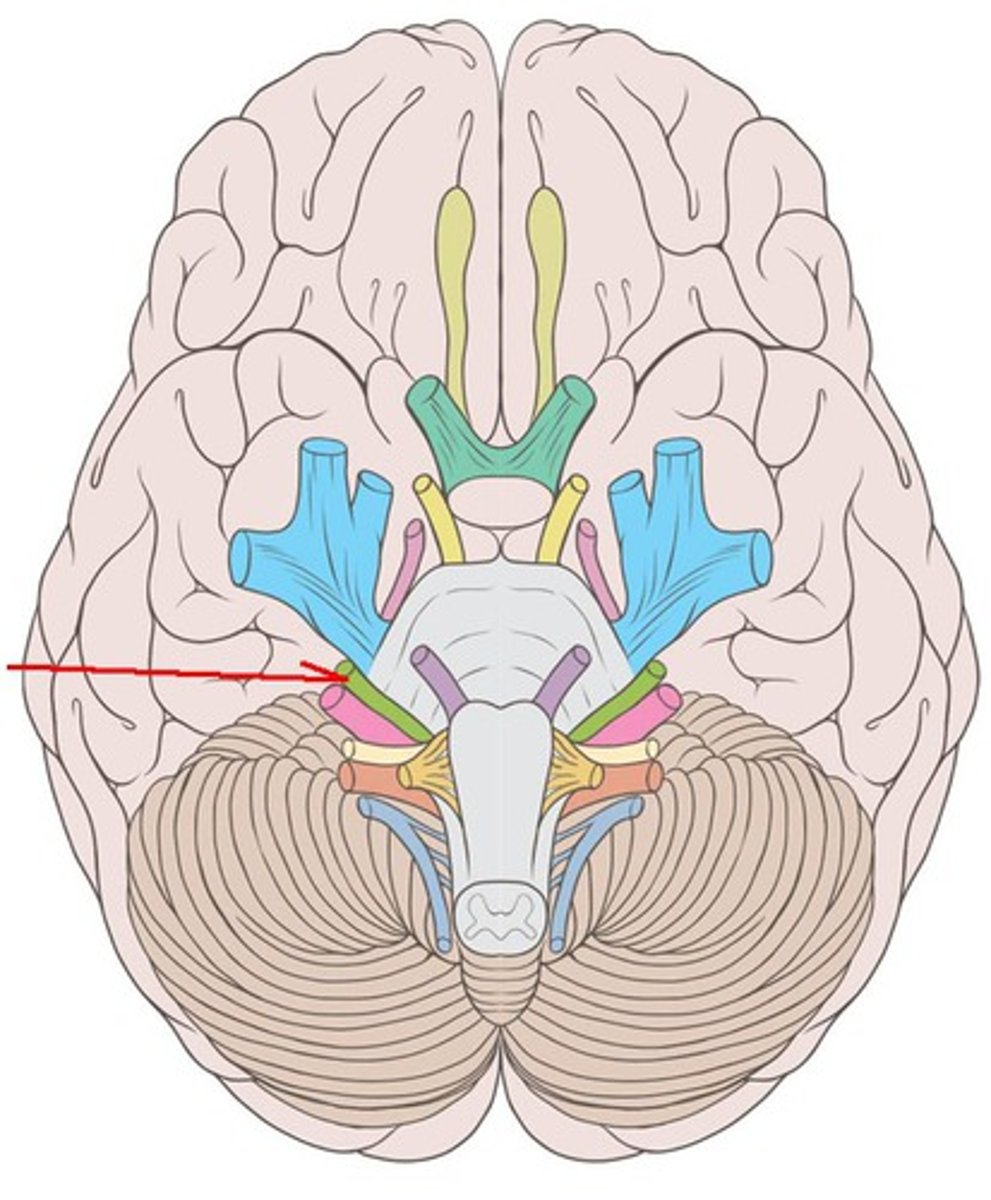

CNVI

abducens nerve: movement of the eyes laterally. Innervates the lateral rectus muscle. motor. emerge near the midline at the border of the pons and medulla, runs up the pons, exit at superior orbital fissure.

CNVII

Facial nerve: taste (anterior 2/3 of tongue), muscles of facial expression, innervation of most salivary glands. Both. Emerge near junction of pons and medulla lateral to emergence of abducens nerves. exit at internal acoustic meatus and stylomastoid foramen.

CNVIII

vestibulocochlear nerve: hearing, balance, and orientation. sensory. Enter the brainstem lateral to (right next to) the facial nerves. Exit at internal acoustic meatus.

CNIX

Glossopharyngeal nerve: receive sensory information from the tonsils, pharynx, middle ear, and posterior tongue and innervates the stylopharyngeus muscle and parotid gland. Both. Emerge posterior to the olive on the lateral aspect of the medulla oblongata. Exit at jugular foramen.

glossopharyngeal nerve

sensory: tonsils, pharynx, middle ear, posterior 1/3 of tongue taste

motor: stylopharyngeus

parotid gland innervation

exit: jugular foramen

CNX

Vagus nerve: provides parasympathetic innervation to organs of the thorax and part of the abdomen and the innervation of muscles of the larynx and pharynx. Both. Emerge caudal to the glossopharyngeal nerves in the same series of rootlets. Exit at jugular formaen.